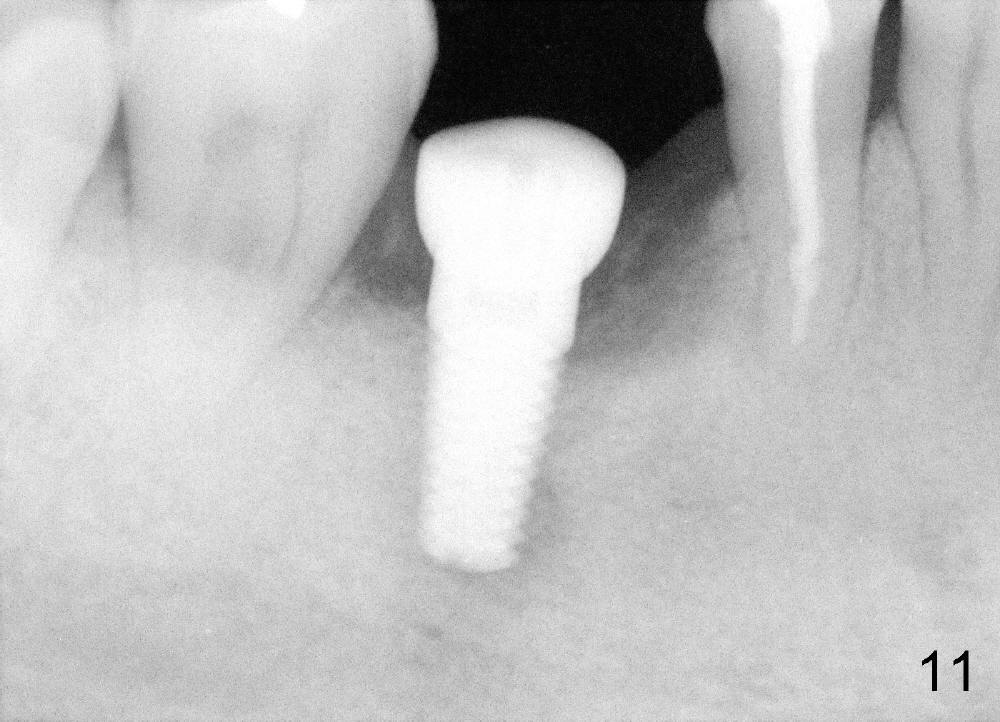

A 46-year-old man has severe periodontitis. The tooth #30 is complicated by incomplete root canal therapy (Fig.1,2). Three months after extraction (Fig.3-5: N: inferior alveolar canal), a 5x14 Tatum tapered implant is placed (Fig.6,7). The problem is that an implant driver is fractured (D in Fig.7), while the implant is being torqued. It takes time and effort to remove the fractured driver, but the implant is solid. The healing screw is placed without difficulty (Fig.8). Since the implant is placed lower than the lingual gingiva (L in Fig.9), a healing cuff is placed 1.5 months after implant placement (Fig. 10 and 11: C) to push the lingual gingiva down. The X-ray appears to show lower bone density around the implant (bone necrosis?), although the implant has no mobility at all. Since the implant is so solid, can we load it, two months after surgery? The lingual gingiva is now lower than the healing cuff (not shown). CT is scheduled to be taken tomorrow. Thanks.